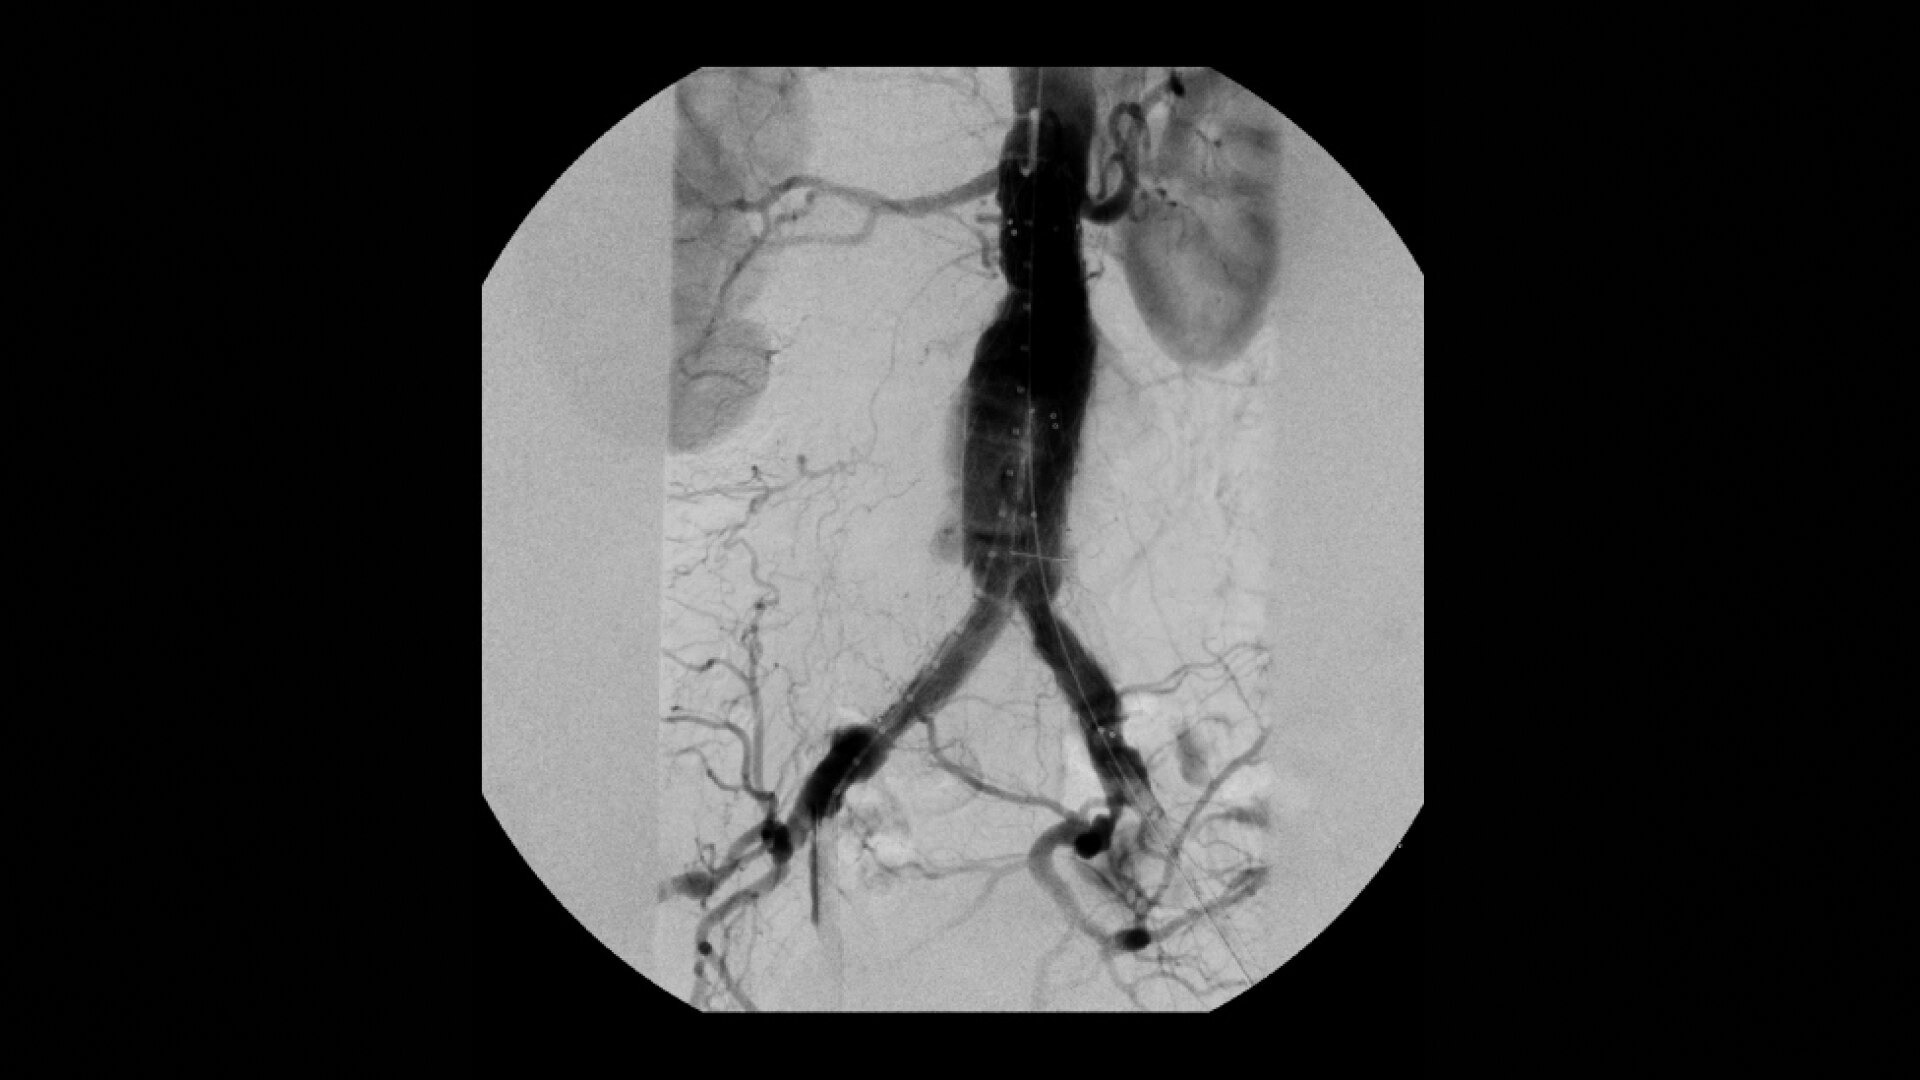

OEC C-arms are used by interventionalists and surgeons to obtain vascular imaging during peripheral to contrast run-off procedures. Superb resolution, even in the presence of motion, enables easy identification of anatomical landmarks and the extremity of the catheter, even as catheter tip moves.

Perform a full leg Bolus Chase in one contrast run with a Preset Profile that includes Motion Tolerant Subtraction, that dynamically adjusts image quality based on presence of motion.

During contrast run-off procedures, easily select contrast type with positive (e.g. Iodine) or negative (e.g. Carbon Dioxide) during subtraction. The OEC Elite CFD cardiovascular package also includes Roadmapping.

Complex vascular procedures require powerful imaging systems. OEC premium C-arms perform in a variety of procedures such as:

•Abdominal aortic aneurysm (AAA) stent and balloon deployment

• Infrarenal aortic aneurysm repair

• Recanalization and stent placement in iliac arteries

• Recanalization of the superior mesenteric artery

• Stent implant in peripheral artery

• Vascular long lesion treatment